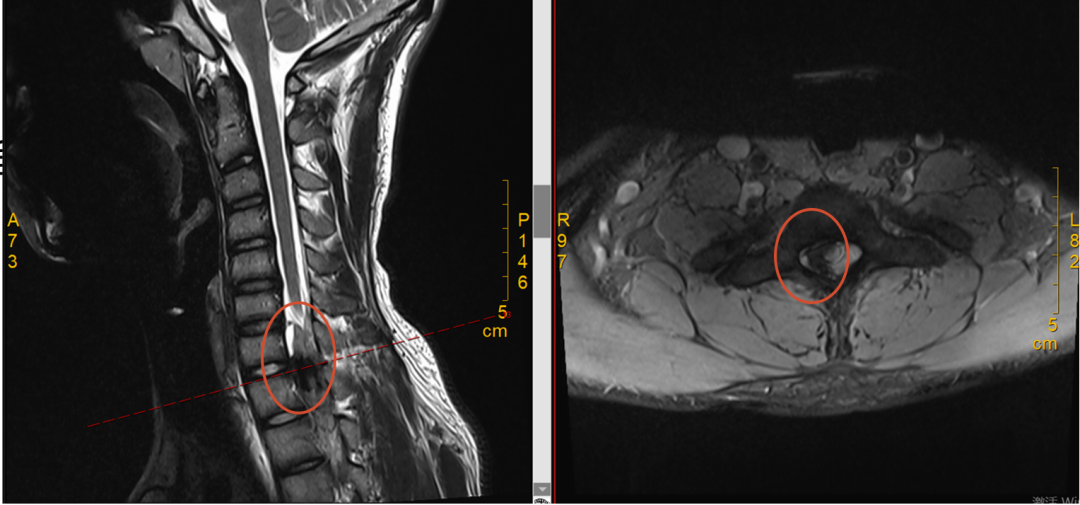

接诊的脊柱外科团队迅速开通绿色诊疗通道。随后的颈椎增强磁共振(MRI)检查,揭示了病因所在——在小吴的颈椎和胸椎交界处(颈 7-胸 1 节段),椎管里长了一个东西,正好压住了控制右上肢的神经。

颈椎增强磁共振显示:颈 7-胸 1 节段的椎管内髓外偏右侧,有一个椭圆形的占位性病变